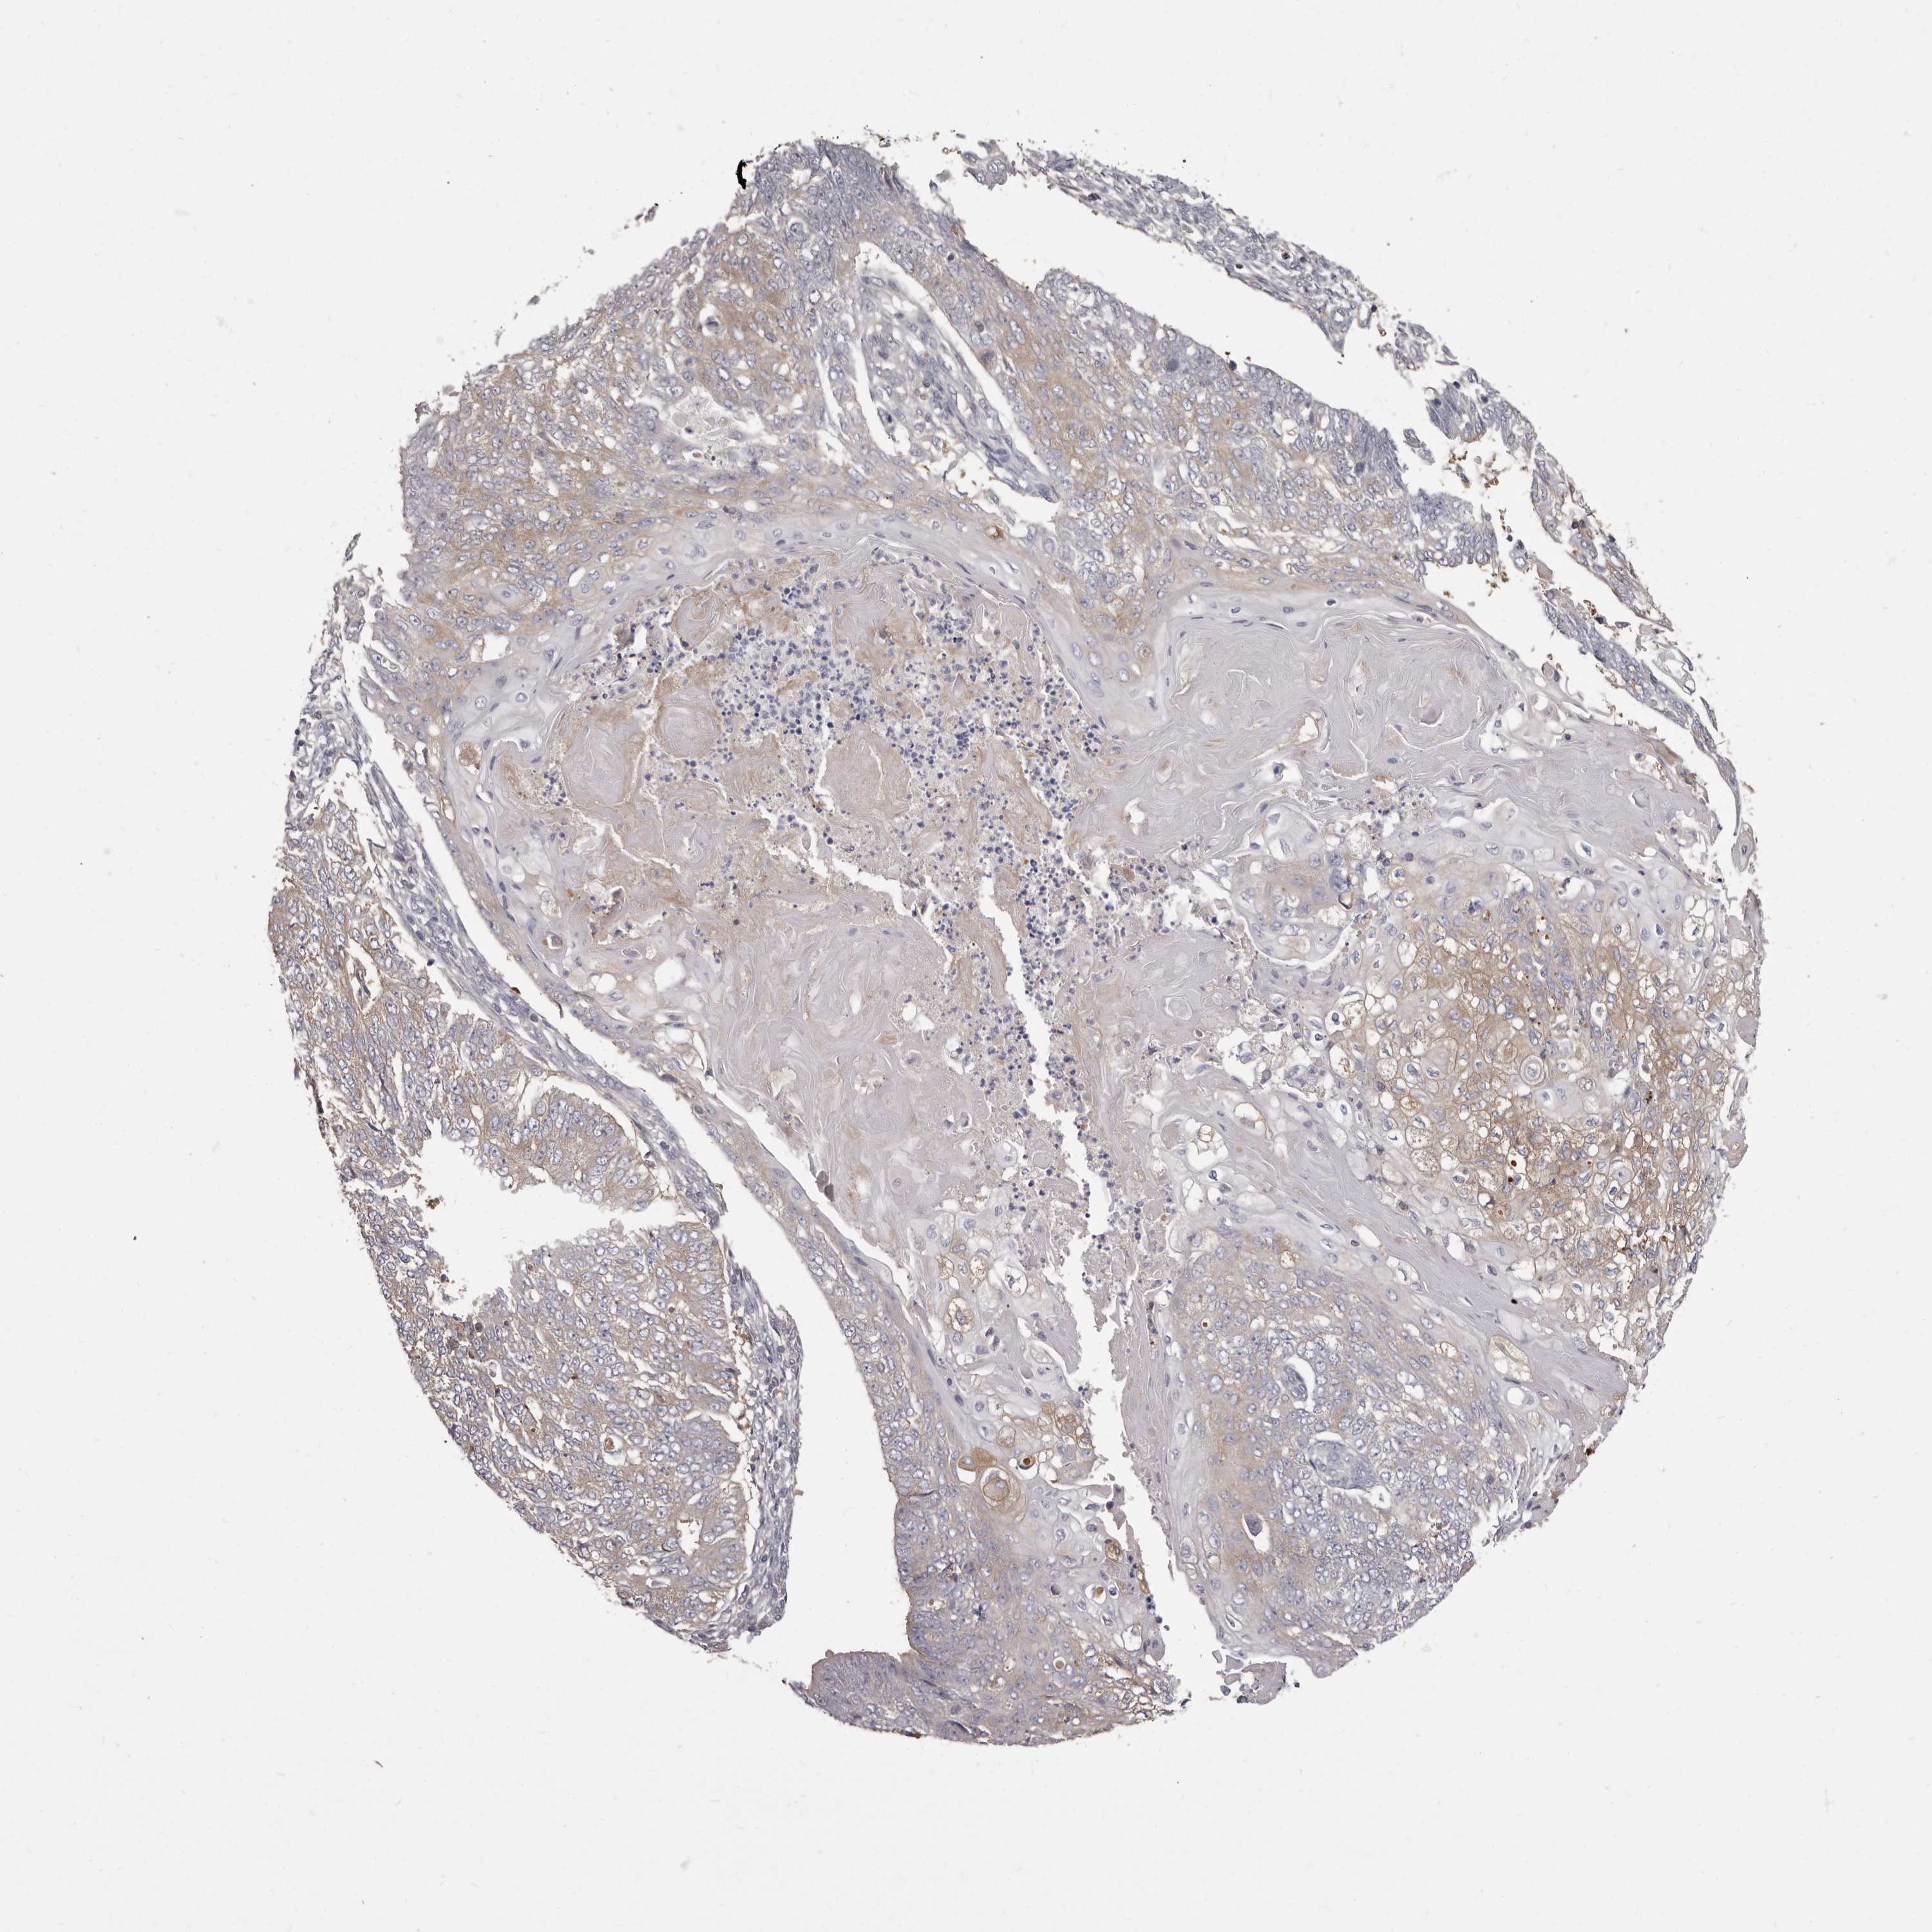

ENDOMETRIAL CANCER - Protein expressioni

A mouse-over function shows sample information and annotation data. Click on an image to view it in a full screen mode. Samples can be filtered based on level of antibody staining by selecting one or several of the following categories: high, medium, low and not detected. The assay and annotation is described here.

Note that samples used for immunohistochemistry by the Human Protein Atlas do not correspond to samples in the TCGA dataset.

Antibody stainingi

Antibody staining in the annotated cell types in the current human tissue is reported as not detected, low, medium, or high, based on conventional immunohistochemistry profiling in selected tissues. This score is based on the combination of the staining intensity and fraction of stained cells.

Each image is clickable and will lead to virtual microscopy that enables deeper exploration of all samples and also displays staining intensity scores, fraction scores and subcellular localization as well as patient and tissue information for each sample.

Antibody HPA029700

Antibody HPA029701

Antibody HPA029702

Antibody HPA029703

Staining

High

Medium

Low

Not detected

Intensity

Strong

Moderate

Weak

Negative

Quantity

>75%

75%-25%

<25%

None

Location

Nuclear

Cytoplasmic/membranous

Cytoplasmic/membranous,nuclear

Adenocarcinoma, NOS

Adenocarcinoma, metastatic, NOS